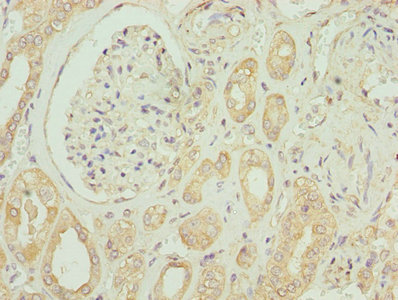

應用范圍:ELISA, IHC, IF

Application Recommended Dilution IHC 1:20-1:200 IF 1:50-1:200 -